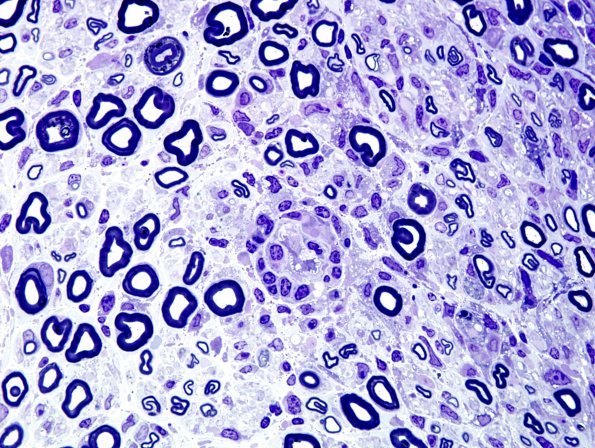

8A2-4 In this case an inflammatory perivascular infiltrate was particularly prominent. (Plastic sections)